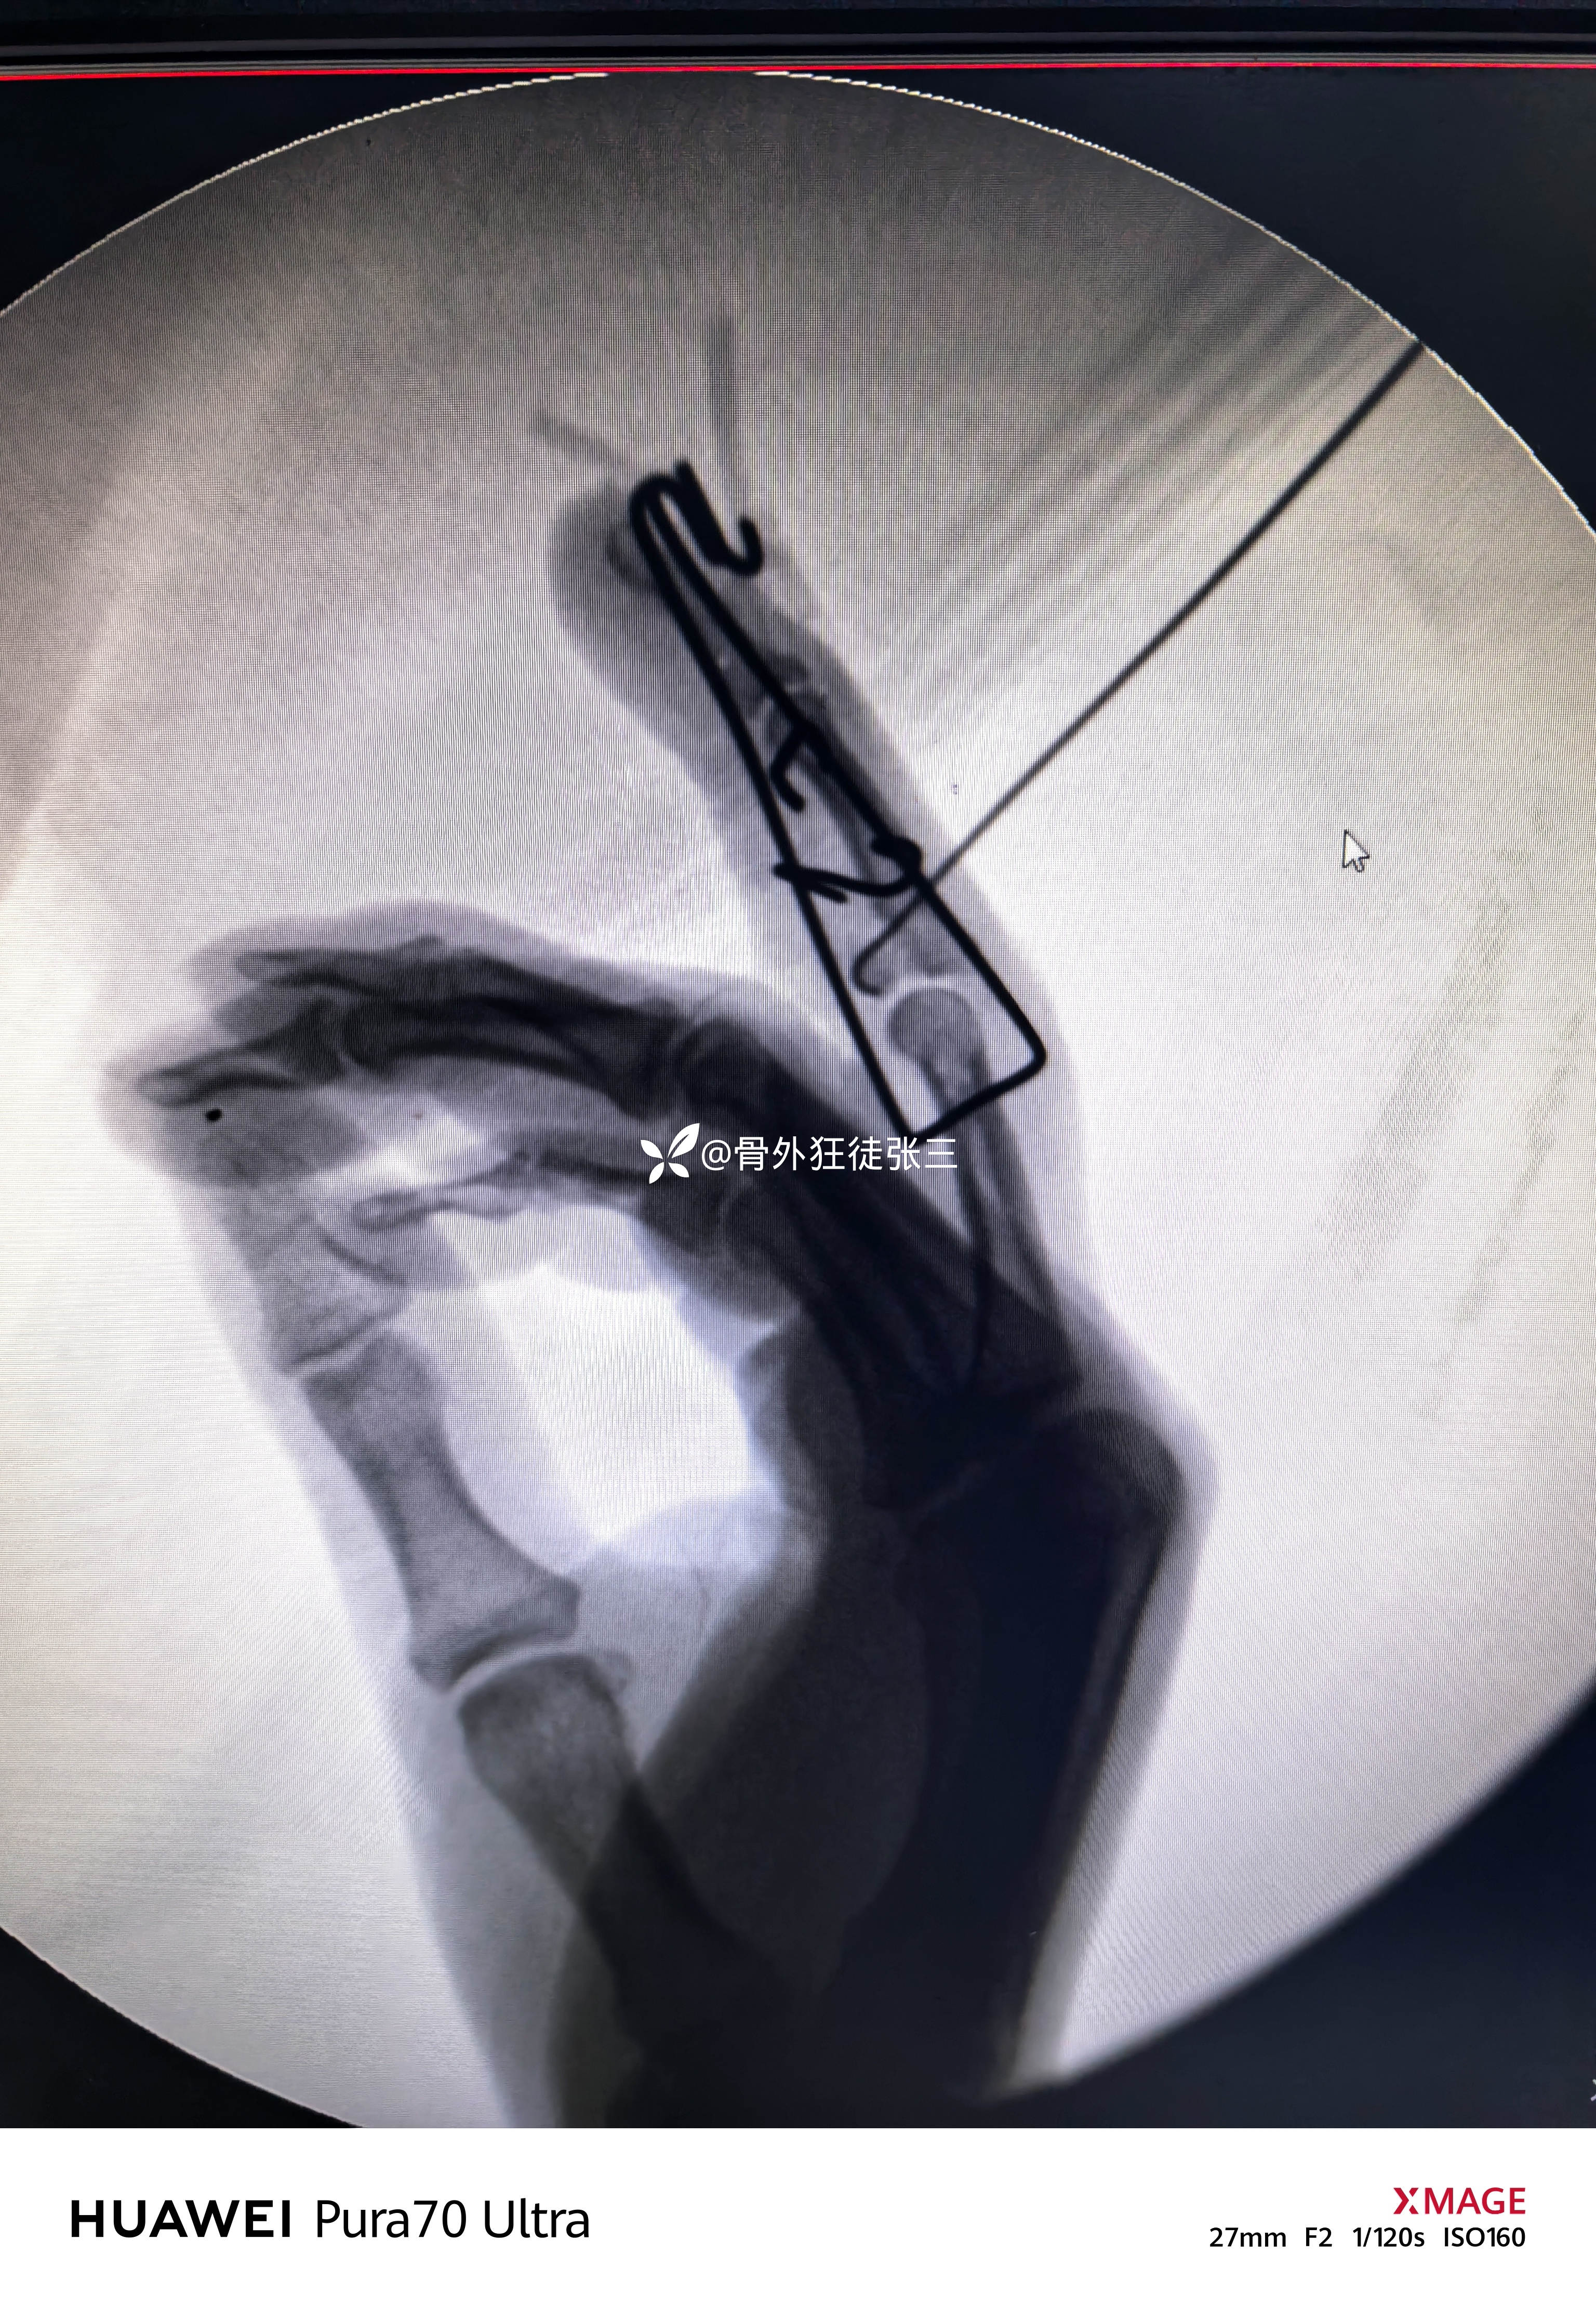

先穿针

“针人针事”

一分钟一根针

折弯,橡皮条牵引

透视发现,无法纠正脱位和骨折